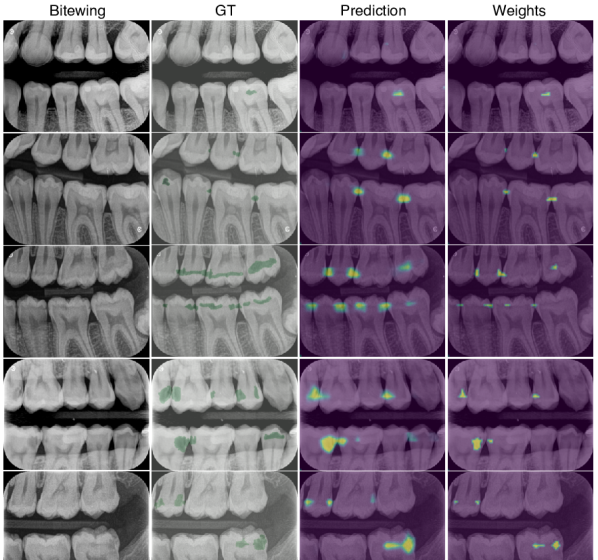

Fig. LABEL:fig:bw shows a positive BWR and EMIL heatmaps. is sensitive and detects all lesions, while is precise and focuses on the most discriminative regions. A colorbar indicates local class probabilities and attention values, respectively. Fig. LABEL:fig:teeth adds a qualitative visualization comparison. Attribution methods such as saliency maps Simonyan et al. (2014), Grad-CAM Selvaraju et al. (2017) or occlusion maps Zeiler and Fergus (2014) (ResNet), as well as DeepMIL, are sensitive to positive cases (rows 1-3) but not precise. Moreover, these methods do not ignore the negative class (row 4), and false negatives are accompanied by false positive visualizations (row 5). This is resolved in Y-Net and EMIL (), and caries may be highlighted although the activation is too low to cross the classification threshold (e.g., row 5, column 8).

fig:bw